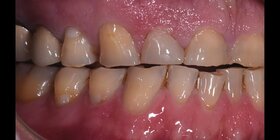

W naszym Centrum stomatologicznym w Lublinie leczenie rozpoczynamy od ustalenia przyczyny starcia zębów. W tym celu przeprowadzamy kilkuetapowe badanie diagnostyczne, zwane deprogramacją Koisa. Polega ona na znalezieniu i rejestracji tzw. Relacji Centralnej, czyli takiego położenia żuchwy, które jest niezależne od działania mięśni. (Gwarantuje nam ono długoczasowe, bezawaryjne funkcjonowanie wykonanej rekonstrukcji zwarcia). W kolejnym etapie analizujemy i oceniamy zwarcie pacjenta na modelach gipsowych w artykulatorze i planujemy leczenie. Przy niewielkim stopniu starcia zębów często postępowanie sprowadza się do korekty zwarcia. W zaawansowanym stopniu konieczna jest odbudowa utraconych tkanek zębów. Stosowane są tu metody zachowawcze (odbudowa specjalnym, dedykowanym materiałem kompozytowym o twardości równej do twardości szkliwa) oraz metody protetyczne tzn. onlye, licówki, korony.

Albo nadbudowujemy zęby materiałem do odbudowy zwarcia (specjalny kompozyt o twardości i śieralności równej tkankom zęba) lub wykonujemy licówki okluzyjne ceramiczne. Leczenie prowadzone jest najczesciej po procesie deprogramacji aby efekt był możliwie jak najbardziej trwały od 250- kompozyt, do 2000- lic. cyrconowa kompozyt- na 1 wizycie, Licówka- kilka dni nieStarte zęby jak odbudować?/Jak zregenerować starte zęby? ▶